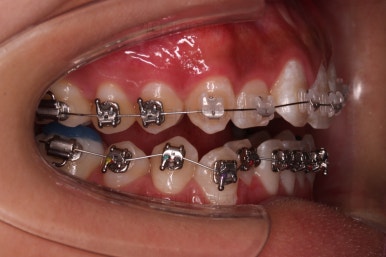

초기 6개월 이내에 어느 정도 치열이 가지런해 졌네요.

중간평가 들어갑니다.

앞니가 많이 뻗쳤나요?

그렇지 않죠.

대신 처음에는 삐뚤어서 가려져 있던 부정교합이 드러나면서 최소한 윗니는 교합을 위해 후방이동이 필요한 상황이긴 했습니다.

미니스크류를 식립을 하고요.

뒤로 뒤로 당겨줍니다.

만족하실 때까지 당겨줍니다.

교합도 신경 써주고요.